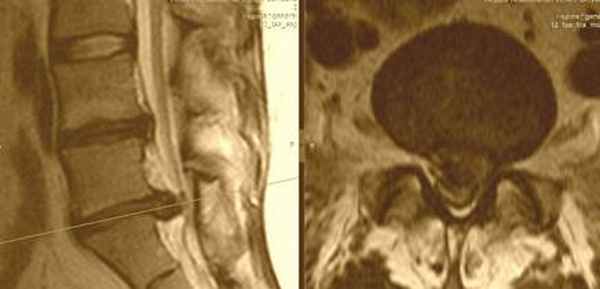

| Медианная грыжа межпозвонкового диска - редкое расположение грыжевого выпячивания, практически всегда - на уровне L5-S1. При большом размере грыжи диска операция выполняется обязательно - для предупреждения нарушения функции тазовых органов. | ![]() |

![]() | Парамедианная грыжа диска - самый часто встречающийся тип грыжи диска, среди пациентов, попадающих к хирургу, когда грыжевой мешок выпячивается в проекции манжетки корешка (самое болезненное место у нерва), а также вызывает компрессию дурального мешка и проходящих в нем нескольких нервных корешков, что смазывает классическую неврологическую картину заболевания. Пациенты с такими грыжами могут достаточно долго - порой до полугода - с переменным успехом лечиться у невролога, пока не попадут на консультацию к нейрохирургу, и, испытав долгий период постоянной боли, - приходят к выводу о неизбежности операции. при этом в послеоперационном периоде многие сожалеют, что так долго терпели, и не знали о том, что операция на позвоночнике - это легкий и быстрый путь жить без боли |

| Латеральная грыжа межпозвонкового диска - второй по частоте вариант расположения грыжи диска, когда хрящ прорывает все связки позвоночника и занимает положение в латеральном кармане - наиболее узком месте у входа нервного корешка в просвет позвоночного канала. Как правило, обычные обезболивающие никогда не снимают полностью боли в ноге при таком расположении грыжи диска. Пациенты, быстро испробовав на себе различные варианты терапии, как только узнают об истинной причине болей - быстро соглашаются на операцию на позвоночнике. | ![]() |

![]() | Фораминальная грыжа диска - редкий тип грыж диска, может сочетаться с истмическим спондилолизом, который в свою очередь дагностируется при спиральной компьютерной томографии. Сложен в диагностике, так как в просвете позвоночного канала грыжи не находят, но боли очень сильные. В этом случае небольшая - 3-4мм грыжа диска располагается в самом узком месте - фораминальном отверстии, где совсем небольшой кусочек хряща может сильно зажать нервный корешок. Лечение исключительно хирургическое. |